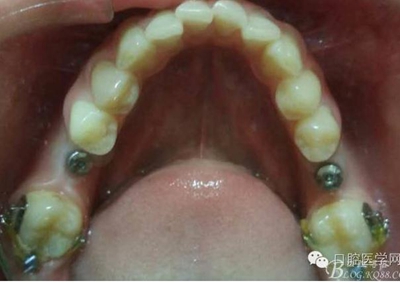

3月后

戴牙后忘記拍口內(nèi)照片了,只有一張X片,下次復(fù)診在補拍 44患者不愿冠修復(fù)

去除了支抗釘,要求患者3個月復(fù)查。